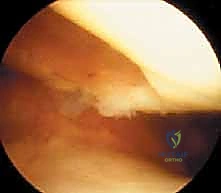

TECH FIG 1 • Arthroscopic view of a full-thickness medial femoral condyle lesion.